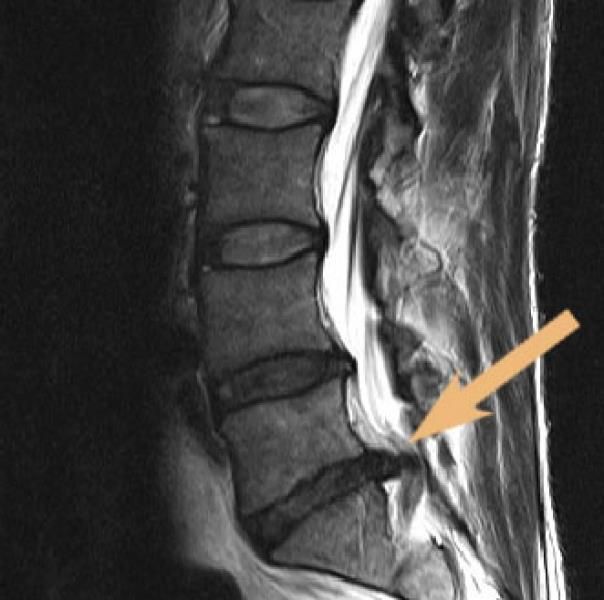

Eine Vielzahl – oft noch junger – Menschen leidet unter Rückenschmerzen, die nicht selten auf Bandscheibenvorfälle zurückzuführen sind. Dank moderner bildgebender Verfahren wie der Magnetresonanztomographie (MRT), auch Kernspintomografie genannt, lassen sich solche Vorfälle heute schnell und präzise diagnostizieren. Diese exakte Lokalisierung bildet die Grundlage für eine zielgerichtete und effektive Therapie.

Wie wird die MRT-gesteuerte PDI-Therapie durchgeführt? Bei der MR-gesteuerten Schmerztherapie handelt es sich um ein besonders präzises Verfahren. So werden per kernspintomographischer Planung in Bauchlage des Patienten feine Nadeln millimetergenau an die schmerzenden Strukturen wie Wirbelgelenke oder Nervenwurzeln sowie ggf. auch an einen Bandscheibenvorfall herangeführt. Nach Kontrolle der Nadellage werden z.B. die Wirbelgelenke infiltriert oder aber eine Nervenwurzel mit betäubenden und entzündungshemmenden Medikamenten umspritzt. Selbstverständlich erfolgt vor jeglicher Therapie eine präzise Analyse des Schmerzes durch die genaue Befragung des Patienten zu seinem Schmerzbild. Anschließend werden diese Befunde mit den Ergebnissen einer kernspintomographischen Untersuchung (MRT) verglichen. Konventionelle Röntgenuntersuchungen haben hier nur eine sehr begrenzte Aussagekraft.

- Die Nervenwurzeln bei Ischiasschmerzen, die entsprechend des jeweils betroffenen Bandscheibensegmentes ins Bein ausstrahlen; Ursachen sind meist Bandscheibenvorwölbungen und Bandscheibenvorfälle oder verschleißbedingte knöcherne Verengungen des Wirbelkanals oder der Nervenwurzel-Austrittslöcher = MRT- gesteuerte periradikuläre Therapie („MRT-PRT“)